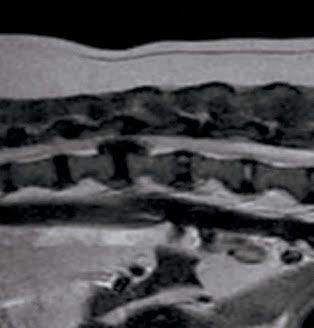

椎間板ヘルニアの症例写真

このように飛び出した内容物が脊髄を圧迫することで、圧迫された部分やその周辺で痛みが生じたり、圧迫された箇所よりも後方全体に麻痺や機能障害が生じたりすることがあります。